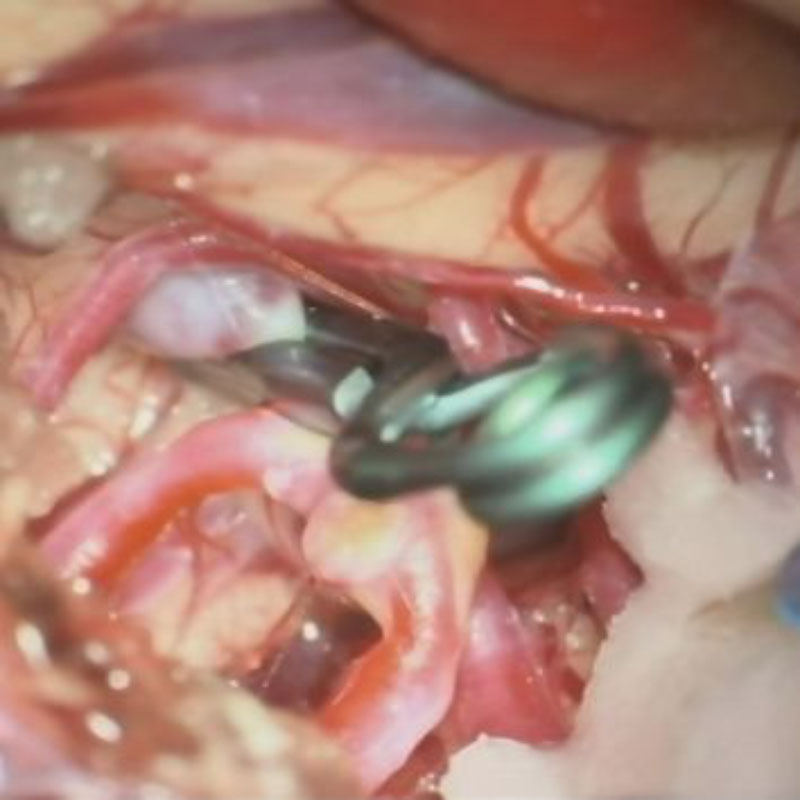

クリップ前

クリップ後